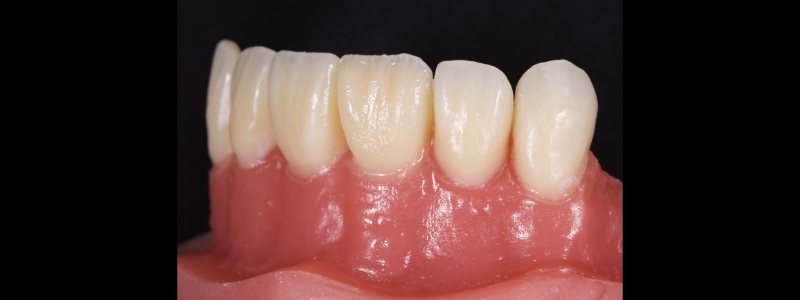

The chromatic enamels are built to full contour in the gingival and mid thirds but are under contoured in the incisal third (Figs. 18 and 19).

The next phase in the build-up is the application of a blue-grey resin mass in between the mamelon effects to create opalescence (Fig. 20). This should be sparing and confined to the incisal 2-3.0 mm. This layer should also be under contoured.

The final layering phase involves applying an achromatic enamel to the incisal third on the facial surface. This is adapted and smoothed with a flat plastic and a #3 brush/modeling resin (Figs. 21 and 22). The restoration is then polished.